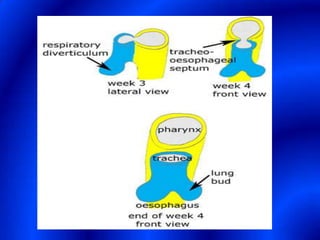

This document provides information about a barium swallow procedure. It begins with an introduction and overview of the embryology and anatomy of the pharynx and esophagus. It then describes the procedure itself, including preparation, technique, views obtained, and indications. Specific conditions that may be examined include pharyngeal and esophageal webs, foreign body impaction, scleroderma, dysphagia, mediastinal masses, and carcinoma. Diagrams are provided to illustrate normal anatomy and various pathological findings.